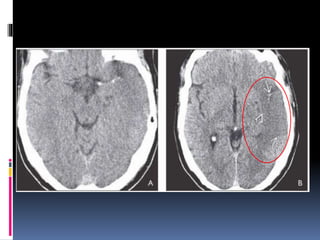

NECT shows hypodensity of the right basal ganglia compared to the normal.

pCT was performed CBV shows markedly reduced blood volume in the right basal

ganglia compared to the normal left side .

CBV in the cortex overlying the basal ganglia infarct appears relatively normal.